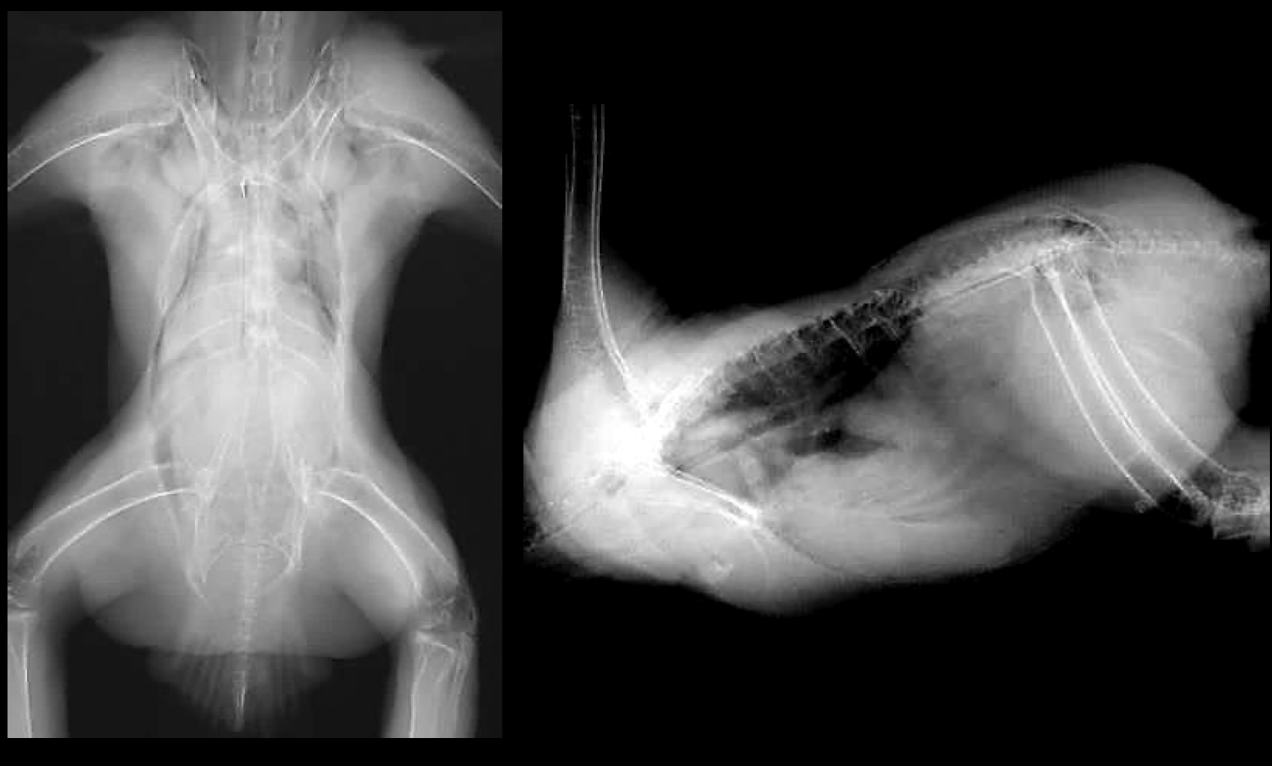

What are the standard radiographic views for avian wings?

VD (ventrodorsal) and caudo-cranial views.

Normal avian wing xray